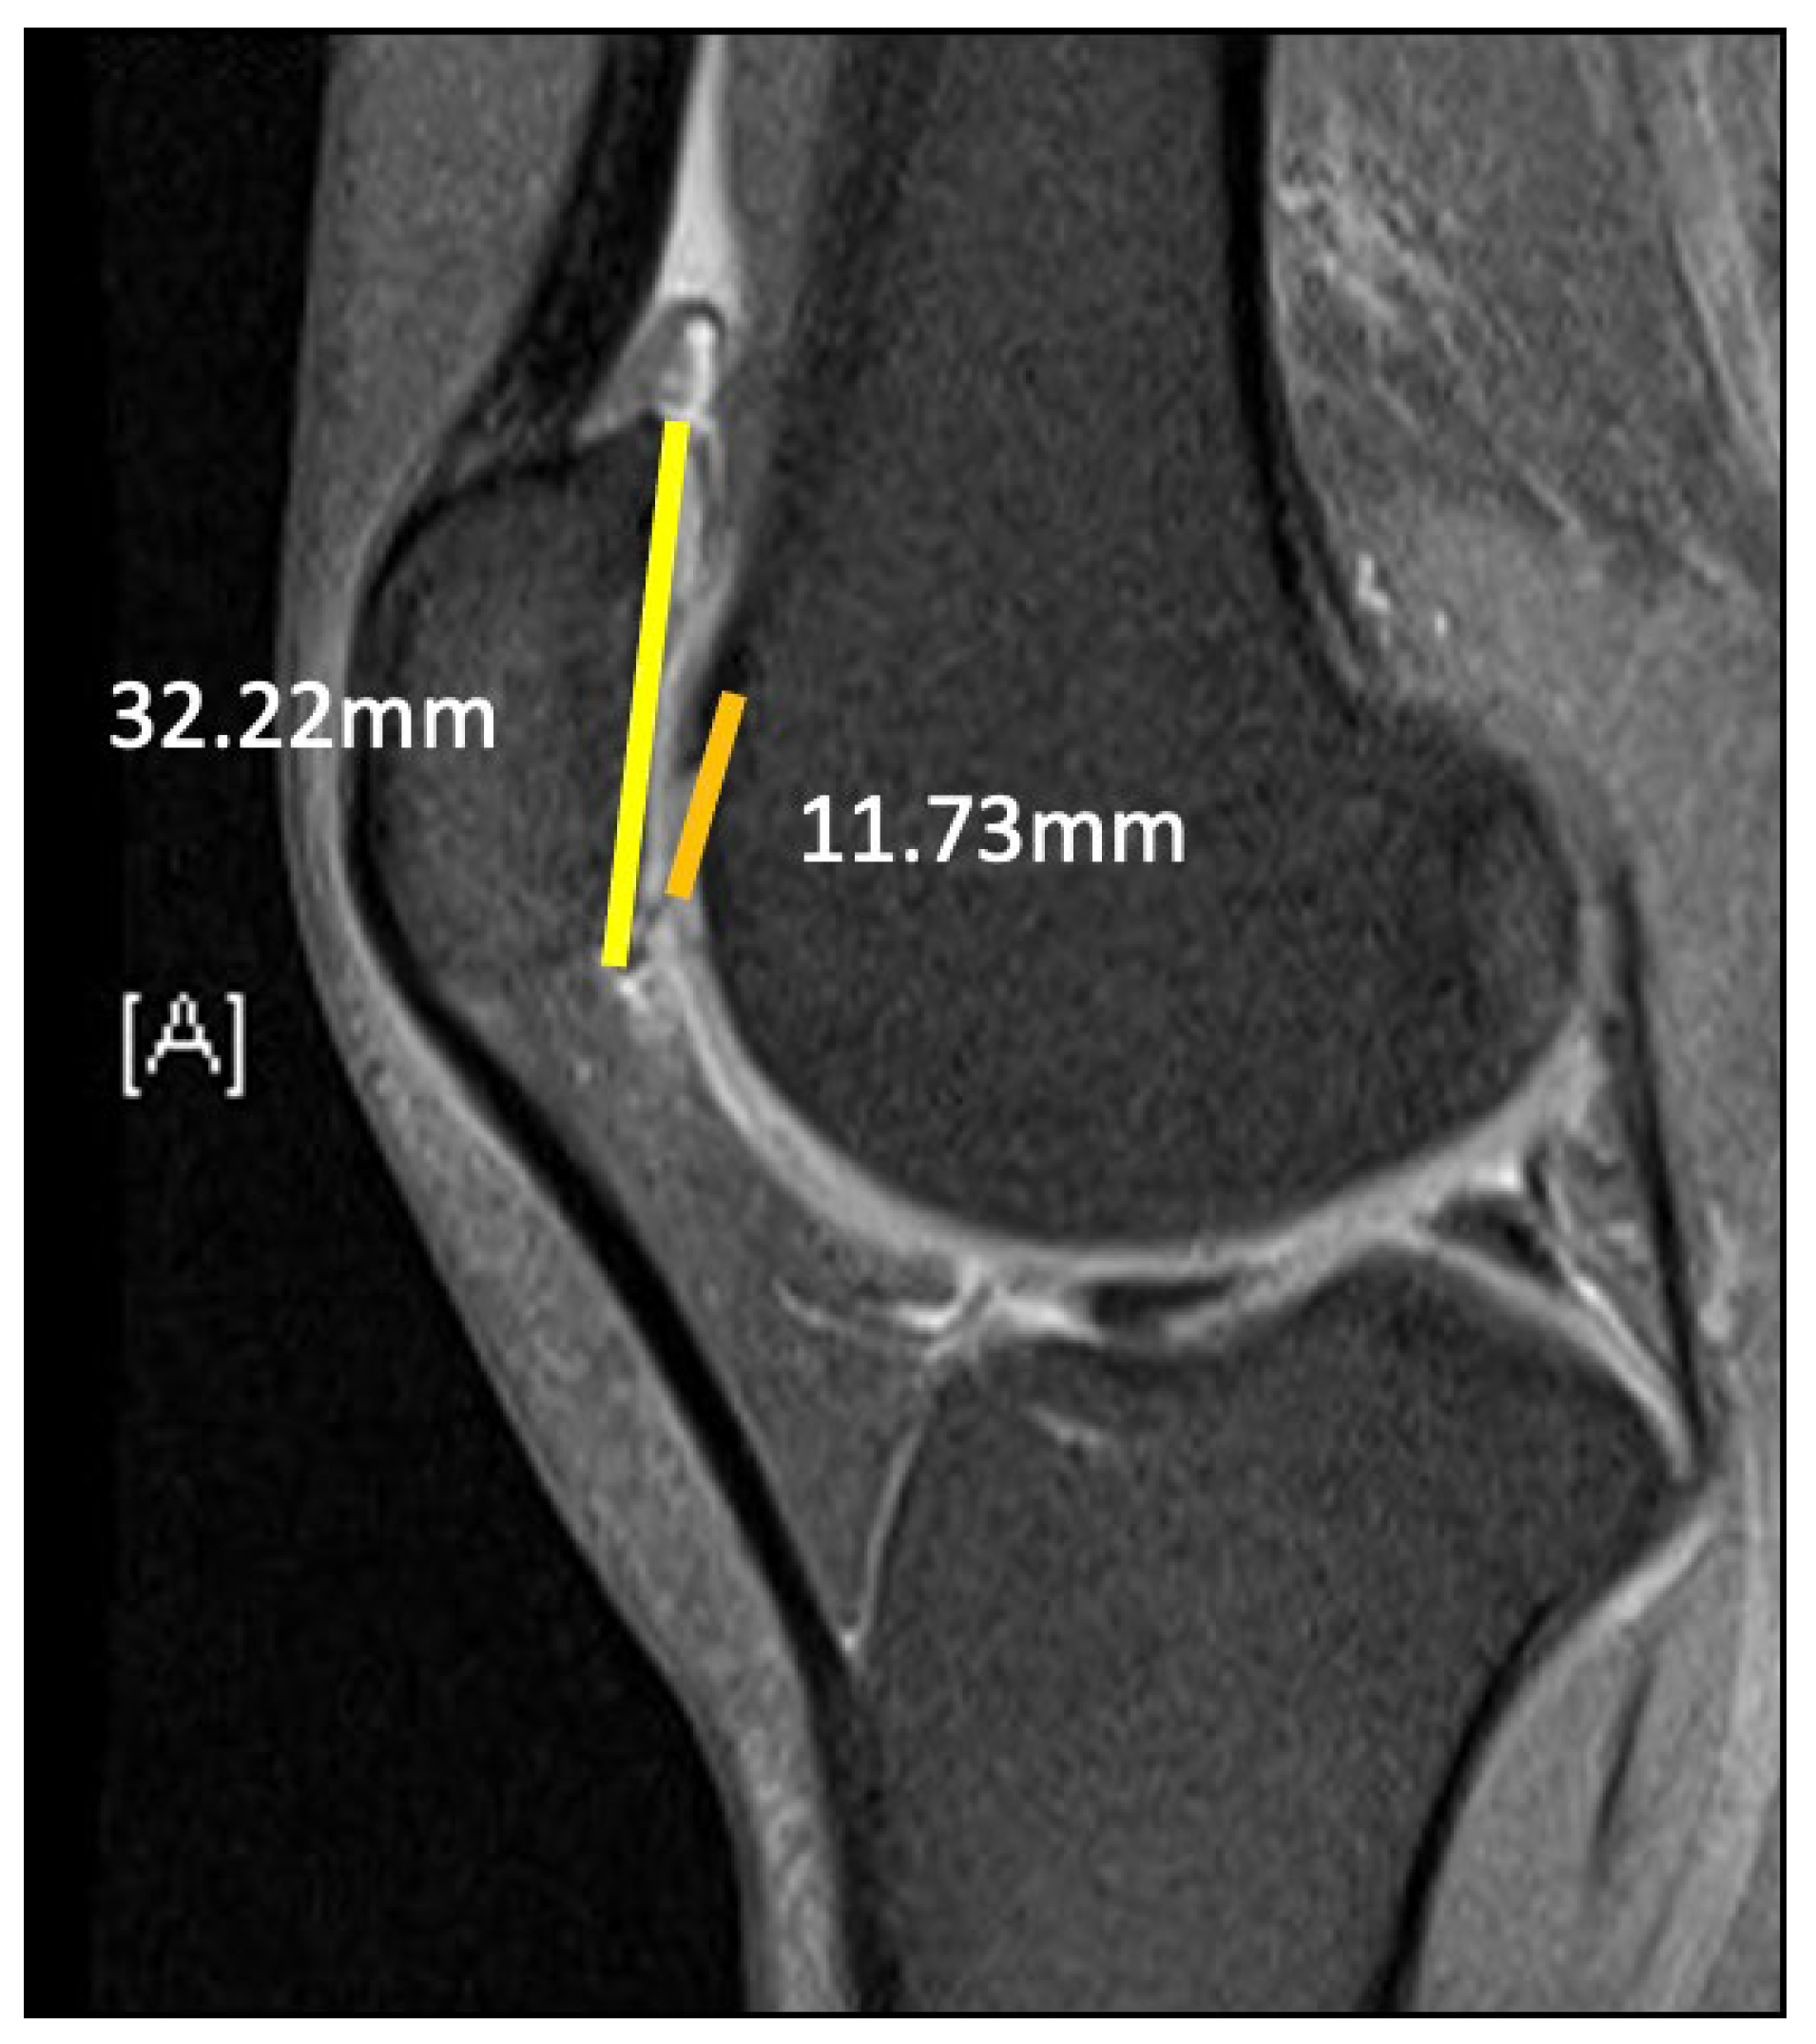

2.1. Case

3.3. TT–TG Distance

3.4. Lateral Patella Tilt